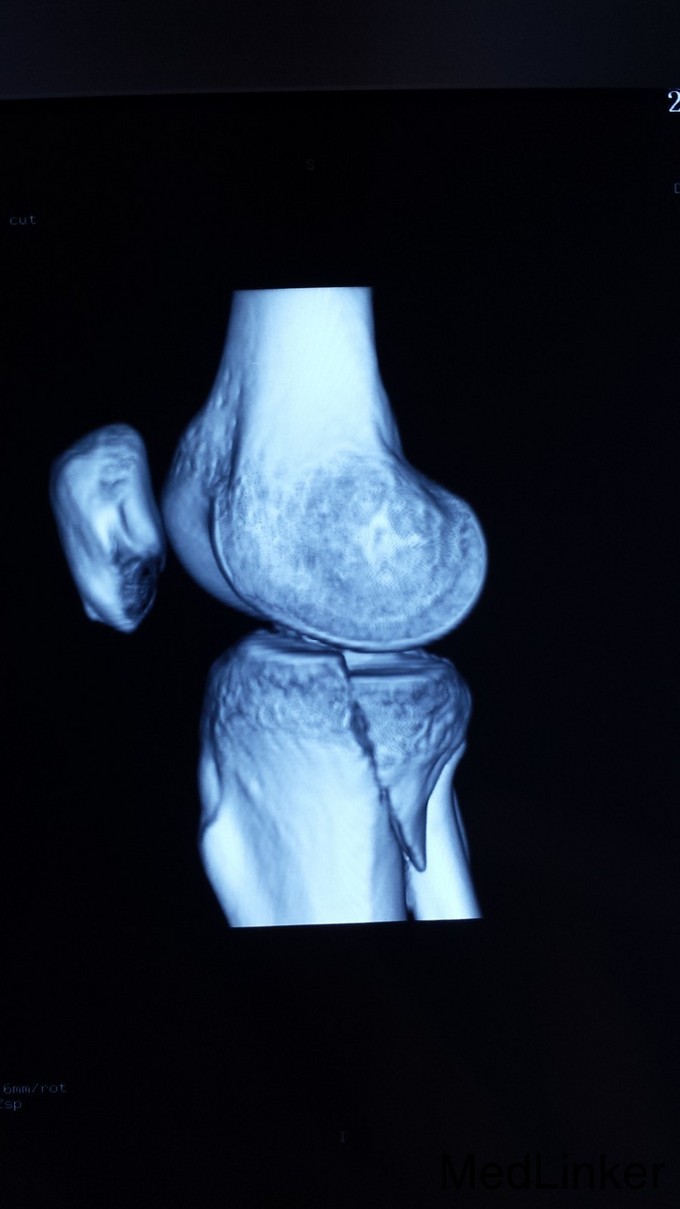

CT三维重建、MRI:膝骨节内侧半月板、外侧半月板前角损伤,前交叉韧带损伤。

光片提示:患者发生累及后内踝的平台骨折。急诊:施行后内、前外侧联合入路手术治疗。先作后内侧入路复位后内髁骨折块及内髁骨折,再作前外侧联合入路复位外髁骨折,同时处理半月板及前、后交叉韧带损伤。